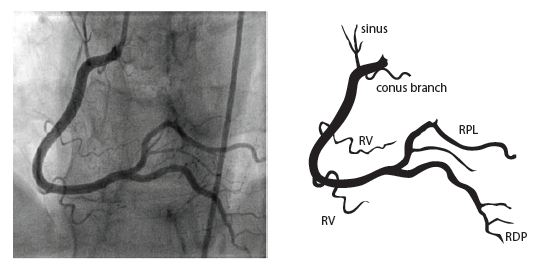

The formal TTE demonstrated a probable apical LV thrombus measuring ~1.5 cm (L) x 1.3 cm and a regional wall motion abnormality (RWMA) with akinesis of the basal inferoseptal and basal mid-inferior myocardium. Note, this RWMA correlates with the EKG findings of STE in the inferior leads II, III, aVF with reciprocal changes in I, aVL and V2. This then prompted a left heart catheterization which demonstrated cut-off of the distal inferior branches of the right posterolateral artery (RPL) which suggests embolism. Note, the anatomic location of this embolism correlates with the echo RWMA and the EKG findings of STE in the inferior leads II, III, aVF with reciprocal changes in I, aVL, V2 (Figure 2). Specifically, the occluded posterior artery is represented on the EKG by the ST depression in V2.

Figure 2. Coronary Anatomy (Image from: https://www.pcipedia.org/wiki/Coronary_anatomy)